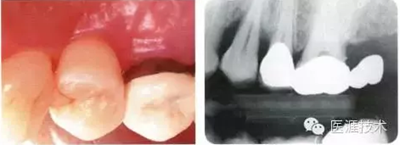

牙根形態(tài)成為局部性風(fēng)險因素的病例

初期治療后左上4的近中有牙槽骨吸收三角區(qū)的凹凸,目前堅持進行維護的狀態(tài)下牙周袋深度仍有6mm。菌斑控制做得很好,牙齦組織緊繃健康,沒有出血現(xiàn)象。